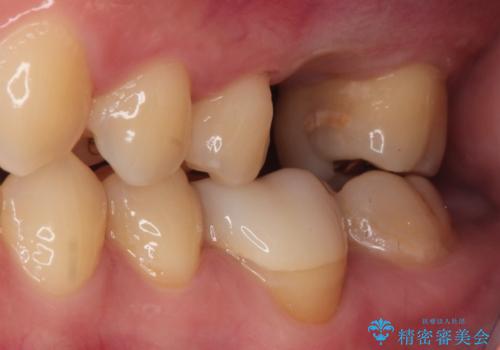

【歯牙移植】親知らずを移植して、インプラントを回避。

- 銀歯の下が大きな虫歯になり、保存困難のためその後の治療計画について悩まれていた患者様です。

患者様と相談し、親知らずを用いて歯牙移植を行いました。